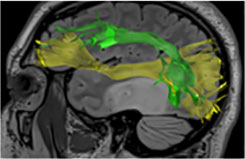

Le cerveau étant parfaitement indolore, la chirurgie est réalisée sous anesthésie locale. Le patient effectue des tests sur la table d’opération, par exemples : bouger le bras, compter, parler etc. Dans le même temps, le neurochirurgien applique à la surface du cerveau une stimulation qui va perturber transitoirement (quelques secondes) et de façon très localisée (quelques millimètres) le fonctionnement cérébral (Figure 1). Ceci permet de localiser avec exactitude les fonctions du cerveau (Figure 2) et donc de retirer la tumeur avec le maximum de sécurité.

Des tests seront réalisés avant l’intervention, en fonction de la localisation de la tumeur : IRM avec tractographie (Figure 3), tests neuropsychologiques…

Figure 3